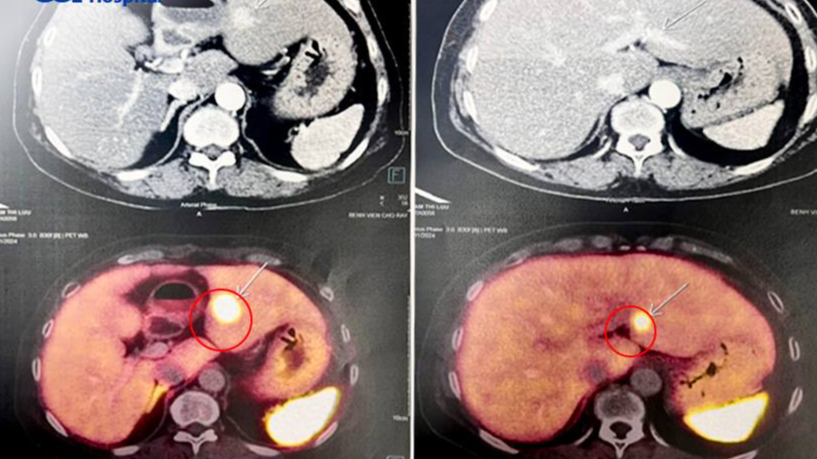

Hình ảnh chẩn đoán các khối u gan, tụy trên CT scan (ảnh đen trắng) và trên DSA là u tuyến nội tiết (màu vàng). Ảnh: BVCC

Bất ngờ, kết quả chụp CT Scan toàn thân cho thấy 6 khối u rải rác khắp cơ thể, gồm 2 khối u tuyến cận giáp hai bên, kích thước 1,2cm và 1,7cm; 1 khối u ở vú phải; một ở gan và 2 u ở tụy. Kết quả chụp mạch máu số hóa xóa nền (DSA) và siêu âm nội soi, bấm sinh thiết, xác định u ở gan và tụy là u thần kinh nội tiết.